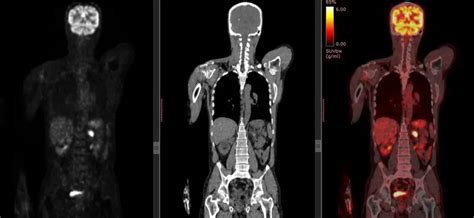

A kivizsgálás orvosi konzultációval kezdődik, amelyet fizikális vizsgálat követ. Az orvos megvizsgálja a nyirokcsomók méretét, állagát és elhelyezkedését. Ezután következik a vérképvizsgálat, amelyből a fehérvérsejtek, vörösvérsejtek és vérlemezkék száma mellett a gyulladásos paraméterek ismerhetők meg. A diagnózis pontosításához képalkotó vizsgálatokra is szükség van. Az ultrahang, CT vagy PET-CT feltérképezi, hogy a betegség lokális vagy kiterjedt formában van-e jelen. A végső diagnózist a biopszia adja, amely során szövetmintát vesznek a megnagyobbodott nyirokcsomóból és/vagy a csontvelőből. A szövettani vizsgálat határozza meg, hogy Hodgkin-limfóma vagy non-Hodgkin-limfóma áll-e fenn, ami meghatározza a kezelés módját és a prognózist.

A nyirokcsomó-daganat kivizsgálása A kivizsgálás orvosi konzultációval kezdődik, amelyet fizikális vizsgálat követ. Az orvos megvizsgálja a nyirokcsomók méretét, állagát és elhelyezkedését. Ezután következik a vérképvizsgálat, amelyből a fehérvérsejtek, vörösvérsejtek és vérlemezkék száma mellett a gyulladásos paraméterek ismerhetők meg. A diagnózis pontosításához képalkotó vizsgálatokra is szükség van. Az ultrahang, CT vagy PET-CT feltérképezi, hogy a betegség lokális vagy kiterjedt formában van-e jelen. A végső diagnózist a biopszia adja, amely során szövetmintát vesznek a megnagyobbodott nyirokcsomóból és/vagy a csontvelőből. A szövettani vizsgálat határozza meg, hogy Hodgkin-limfóma vagy non-Hodgkin-limfóma áll-e fenn, ami meghatározza a kezelés módját és a prognózist.